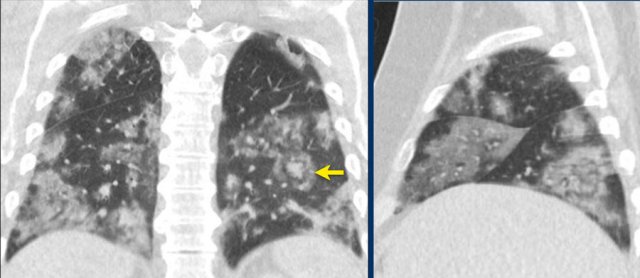

CO-RADS 5 CO-RADS 5

CORADS 5

Case 1

Multifocal GGO and consolidation

Case 2

10 days of complaints.

CT: bilateral multifocal GGO, vascular thickening (circle), subpleural bands (arrow).

PCR: positive

Case 3

Eleven days of complaints

CT findings: Bilateral GGO and consilidation, basal preference, vascular thickening (circle).

Case 4

CT findings: multifocal areas of groundglass and consolidation

Case 5